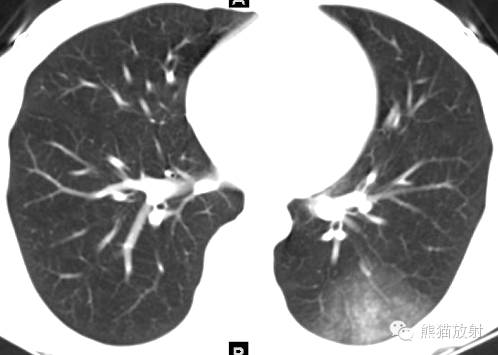

女,19岁,每次来月经时咯血。

CT诊断:结合病史,考虑左下肺子宫内膜异位症(渗出型),建议月经间期复查。

诸病灶分别如下图中圆圈所示: